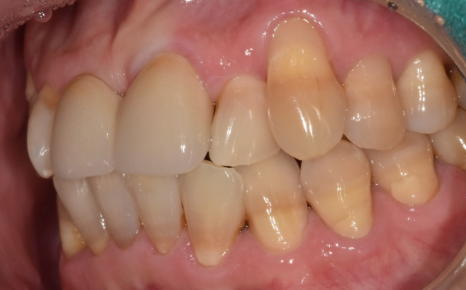

이 환자분이 저희 병원에 오시게 된 이유들은 다음과 같습니다.

230413

왼쪽 앞니가 아래로 더 내려앉는 느낌

찬 것만 먹어도 시린 증상

앞니 사이 틈이 점점 넓어지는 변화

시간이 지날수록 위의 증상이 심해져서 고민하고 계셨습니다.

입안을 확인했을 때,

해당 부위 잇몸 안쪽으로 치석이 보였습니다.

230413 잇몸 내려감으로 길어진 치아, 방치하면 안 되는 원인, 증상, 이유

정확한 상태 확인을 위해 엑스레이 촬영과 검사를 진행한 결과,

치석으로 인해 잇몸병이 진행되면서

잇몸뼈가 일부 녹아 있는 상태였습니다.

230413 / 230417